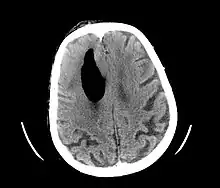

Pneumocephalus is the presence of air or gas within the cranial cavity. It is usually associated with disruption of the skull: after head and facial trauma, tumors of the skull base, after neurosurgery or otorhinolaryngology, and rarely, spontaneously. Pneumocephalus can occur in scuba diving, but is very rare in this context.

| Pneumocephalus and comminuted fracture of the frontal sinus |

CT scans of patients with a tension pneumocephalus typically show air that compresses the frontal lobes of the brain, which results in a tented appearance of the brain in the skull known as the Mount Fuji sign.[1][2][3] The name is derived from the resemblance of the brain to Mount Fuji in Japan, a volcano known for its symmetrical cone. In typical cases, there is a symmetrical depression near the midline (such as the crater of a volcano), due to intact bridging veins.[3] Its occurrence seems to be limited to tension pneumocephalus (not occurring in pneumocephalus without tension).[4] The sign was first described by a team of Japanese neurosurgeons.[5]